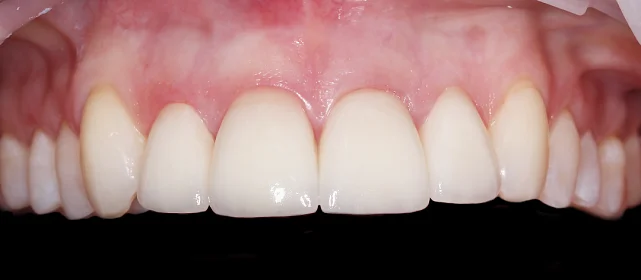

Зубы выровнены, смыкание нормализовано. Установлены несъёмные ретейнеры на обе челюсти, сняты сканы для ретенционных кап.

Решение: Поставили прозрачные элайнеры Click — начали с компактного набора из 20 кап. Основной комплект сделал основной объем работы, но для финальной доводки понадобился дополнительный набор из 10 кап. Итого 30 кап за 23 месяца. Результат — зубы на месте, смыкание в норме. Зафиксировали ретейнеры на обе челюсти, сняли сканы для ретенционных кап.